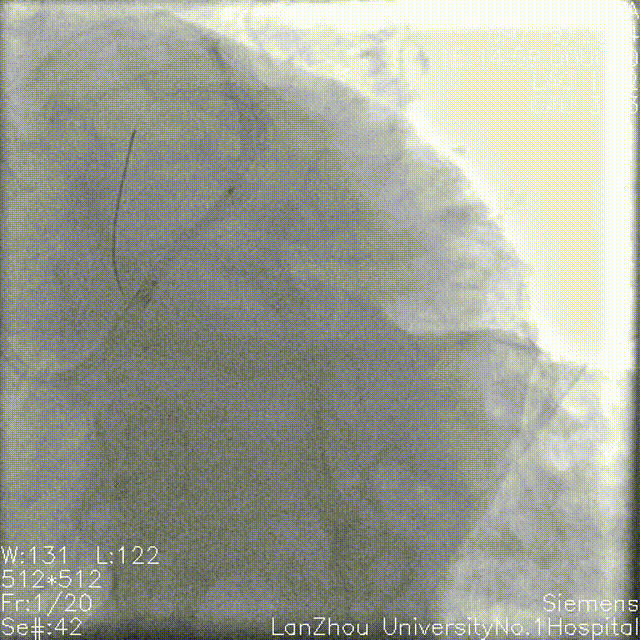

复查造影后再次复查前降支IVUS

前降支近中段支架膨胀不全;

遂3.5mm球囊高压扩张;

结合术后IVUS,考虑该处钙化严重及钙化小结导致IVUS导管及球囊无法通过。

复查造影支架贴壁良好

回旋支支架植入后因支架及钙化原因,IVUS导管无法推送至中段以后,遂仅对回旋支开口支架IVUS检查。

回旋支开口支架后扩后行IVUS检查:支架贴壁膨胀良好。